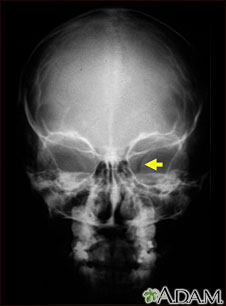

Neurofibromatosis I, agrandamiento de la abertura óptica

Esta radiografía muestra el cráneo de un niño con neurofibromatosis (NF-1). Este niño desarrolló trastornos visuales y se le diagnosticó un glioma (tumor en un nervio) en el nervio óptico. El tumor ha ensanchado el orificio óseo (foramen óptico), a través del cual pasa el nervio óptico, tal como se puede observar en la parte derecha de la imagen.